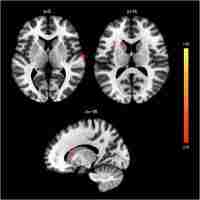

| Abstract | Objective: Clinically, it is very difficult to distinguish between major depressive disorder (MDD) and bipolar disorder (BD) in the period of depression. Increasing evidence shows that the insula is important in depression. We aimed to compare the resting-state functional connectivity (rsFC) of insular subregions in patients with MDD and BD in depressive episodes (BDD), who had never experienced manic or hypomanic episodes when they were scanned to identify biomarkers for the identification of two diseases. Method: We recruited 21 BDD patients, 40 MDD patients and 70 healthy controls (HC). Resting-state functional magnetic resonance imaging (rs-fMRI) was performed. BDD patients had never had manic or hypomanic episodes when they were scanned, and the diagnoses were determined by follow-up. We divided the insula into three parts including the ventral anterior insular cortex (v-AIN), dorsal anterior insular cortex (d-AIN) and posterior insula (PI). The insular-based rsFC was compared among the three groups, and an analysis of the correlation between the rsFC value and clinical scale was carried out. Results: BDD and MDD patients demonstrated decreased rsFC from the v-AIN to the left superior /middle frontal gyrus compared with the HC group. Versus MDD and HC groups, BDD patients exhibited decreased rsFC from the v-AIC to the area in the left orbital frontal gyrus and left superior temporal gyrus (included temporal pole), from the PI to the right lateral postcentral gyrus and from all three insular subregions to the somatosensory and motor cortex. Meanwhile, a correlation between the rsFC value of the PI-right lateral postcentral gyrus and anxiety score was observed in patients. Conclusion: BDD and MDD patients indicate similar decreases in insular connectivity in the dorsal lateral frontal regions, and BDD patients have specific decreased insular connectivity, especially in the somatosensory and motor cortex, which may be used as imaging evidence for clinical identification. |